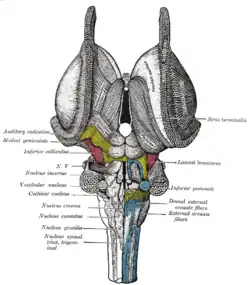

Superficial dissection of brain-stem. Ventral view. Dissection of brain-stem. Dorsal view.

Dissection of brain-stem. Dorsal view. External capsule